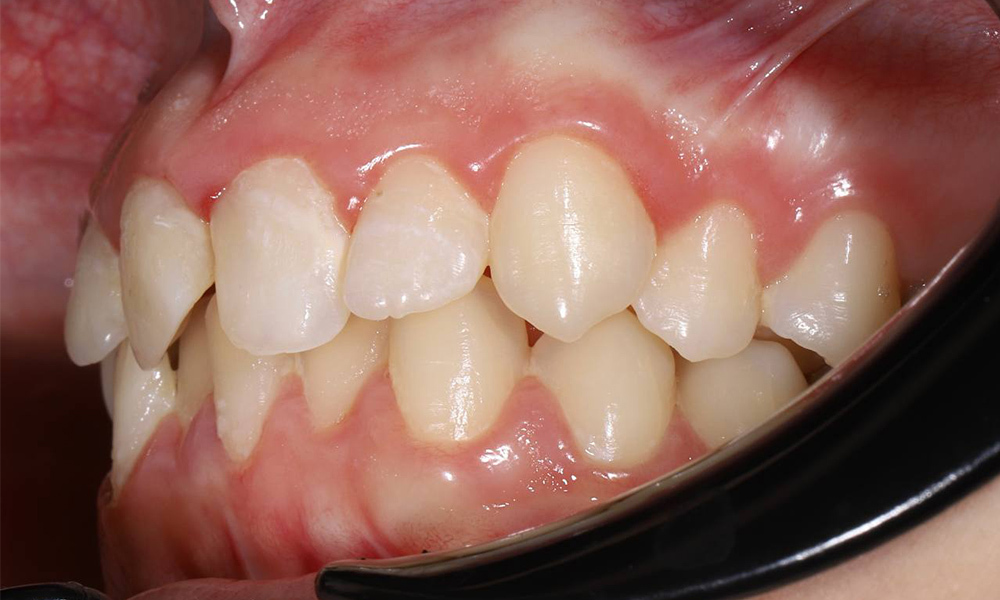

Коррекция прикуса и выравнивание зубов в подростковом возрасте